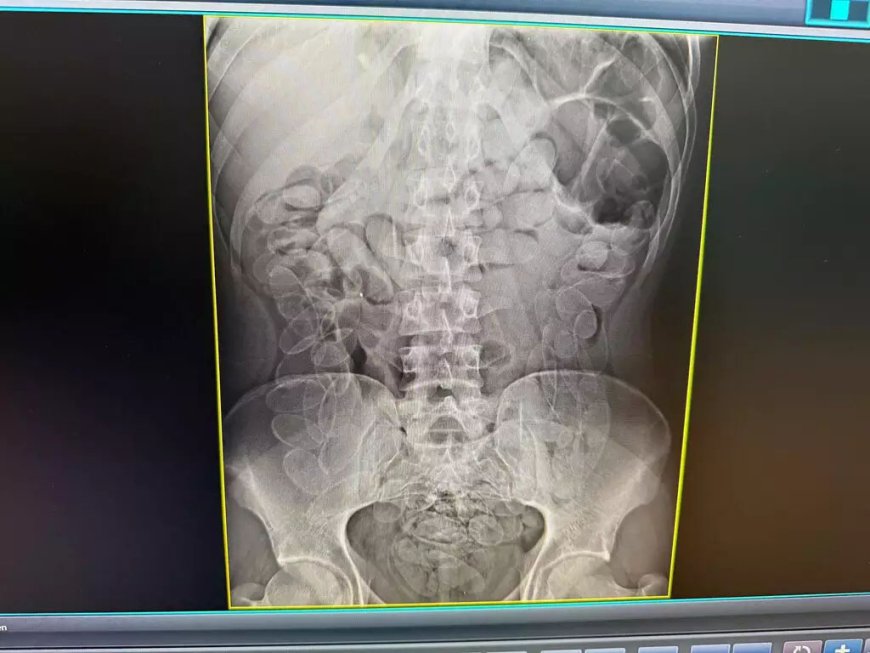

Jovem boliviano de 24 anos foi detido no Posto de Fiscalização Esdras, em Corumbá, após ingerir 90 cápsulas de cocaína. A abordagem ocorreu durante uma operação conjunta da Receita Federal, Polícia Militar e Mapa. O passageiro apresentava sinais de nervosismo e relatou ter ingerido a droga, sendo imediatamente encaminhado à Santa Casa local. Lá, permaneceu sob acompanhamento médico até que a expulsão das cápsulas fosse concluída com segurança.